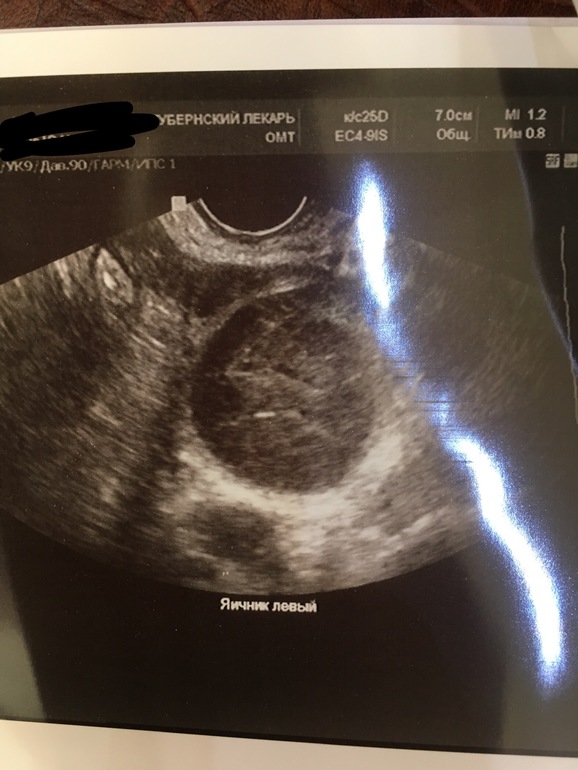

Узи, ничего не поняла 😂

УЗИ, Фолликулометрия

Была овуляция или нет

Девчонки, помогите!!!!! Сделала УЗИ... Большой доминантный фолликул